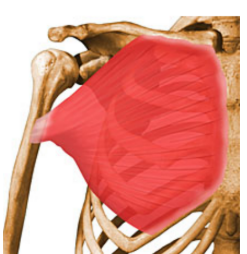

Deltoid | Acromion process, anterior border of lateral 1/3 clavicle, lower lip of crest of spine | Deltoid tuberosity | Anterior flexes and medially rotates Middle abducts Posterior extends and laterally rotates | Axillary nerve |